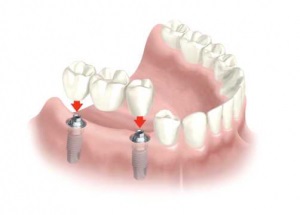

molarilor de minte au două avantaje semnificative. În primul rând, ele sunt cea mai bună opțiune pentru un suport punte (structura de mai mulți biți). In absenta acestei benzi pentru proteze dentare, instalate de obicei implanturi speciale (structura fiind introduse în țesutul osos al maxilarului), și este costisitoare și dureroasă. În al doilea rând, molarii de minte - o dantura de mestecat, descărcare sarcina asupra altor „consumatori“. Prin urmare, nu este nevoie de a elimina Grupul celor Opt, în cazul în care: